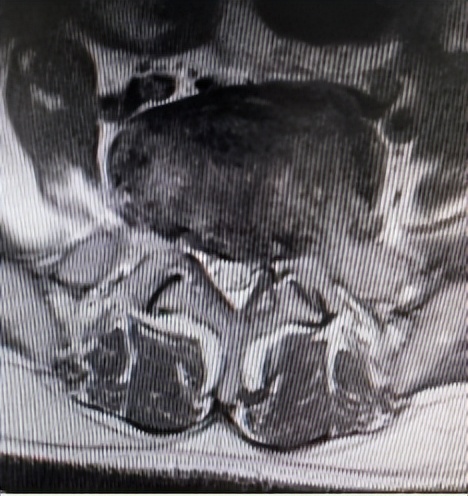

腰3/4、腰4/5两个节段椎管狭窄

66岁男性患者,腰3/4、腰4/5两个节段椎管狭窄,左下肢放射性疼痛、麻木2个月余,间歇性跛行,保守治疗无效。其爱人9年前患腰椎间盘突出症,副主任医师石立刚利用微创椎间孔镜治疗后,至今效果满意。此次慕名前来。